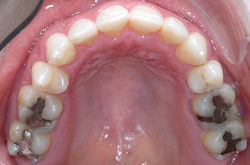

上あご・正面・下あご

before

after